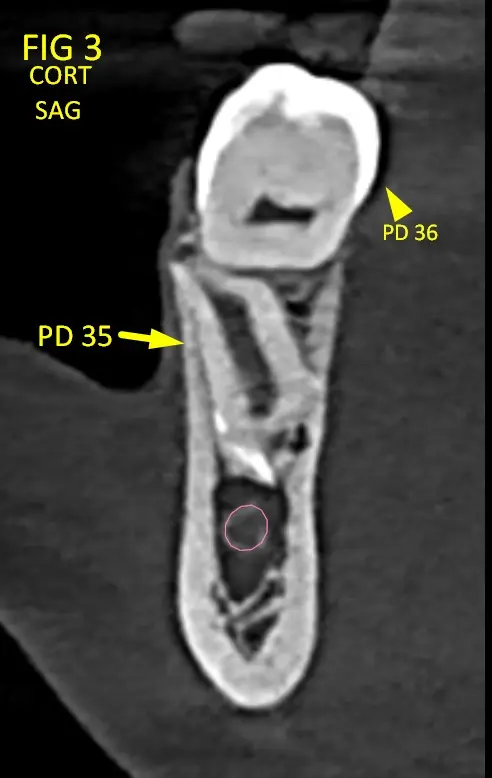

En la reconstrucción tomográfica se evidencia (Fig.1):

• Pieza 45(Fig. 2) (Fig. 2B): retenida, con posición distoangular.

• Pieza 35(Fig. 3) (Fig. 3B): retenida, con orientación en retroversión hacia la base mandibular.